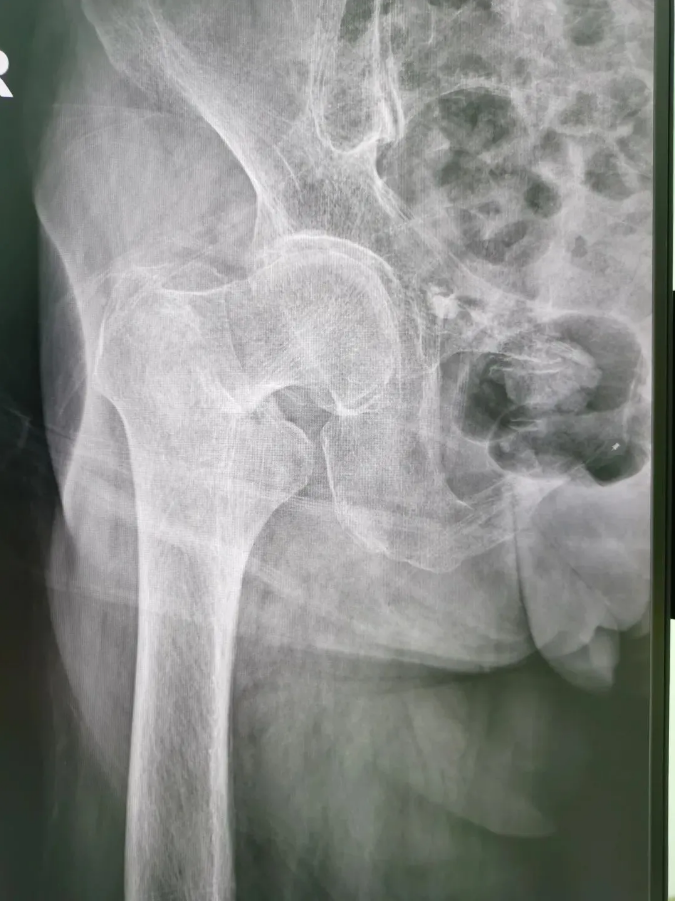

ÊõǰX¹â

½ñÄê91ËêµÄ³ÂÆÅÆÅ£¬£¬£¬£¬£¬£¬£¬9Ô·ÝʱÔÚ¼ÒʧÉ÷ˤµ¹£¬£¬£¬£¬£¬£¬£¬ÓÒÍβ¿×ŵأ¬£¬£¬£¬£¬£¬£¬µ±Ï¸ÐÓ¦÷Ų¿Ç¿ÁÒÌÛÍ´²¢Ô˶¯ÊÜÏÞ¡£¡£¡£¡£¡£¡£ÎªÇó½øÒ»²½ÖÎÁÆ£¬£¬£¬£¬£¬£¬£¬µ½Ë³µÂÇå¾²Íâ¿ÆÒ½Ôº¹ÇÈýÇø¾ÍÕ£¬£¬£¬£¬£¬£¬¸ÃÇøÖ÷ÈÎÑîÉýƽÖ÷ÈÎΪÆäÕïÁÆ£¬£¬£¬£¬£¬£¬£¬±»Õï¶ÏΪ¡°ÓҹɹǾ±¹ÇÕÛ¡±£¬£¬£¬£¬£¬£¬£¬Ðè¾ÙÐÐÓҹɹǾ±¹ÇÕ۾Ƥ±ÕºÏ¸´Î»¿ÕÐÄÂݶ¤ÄÚÀο¿ÊÖÊõ¡£¡£¡£¡£¡£¡£